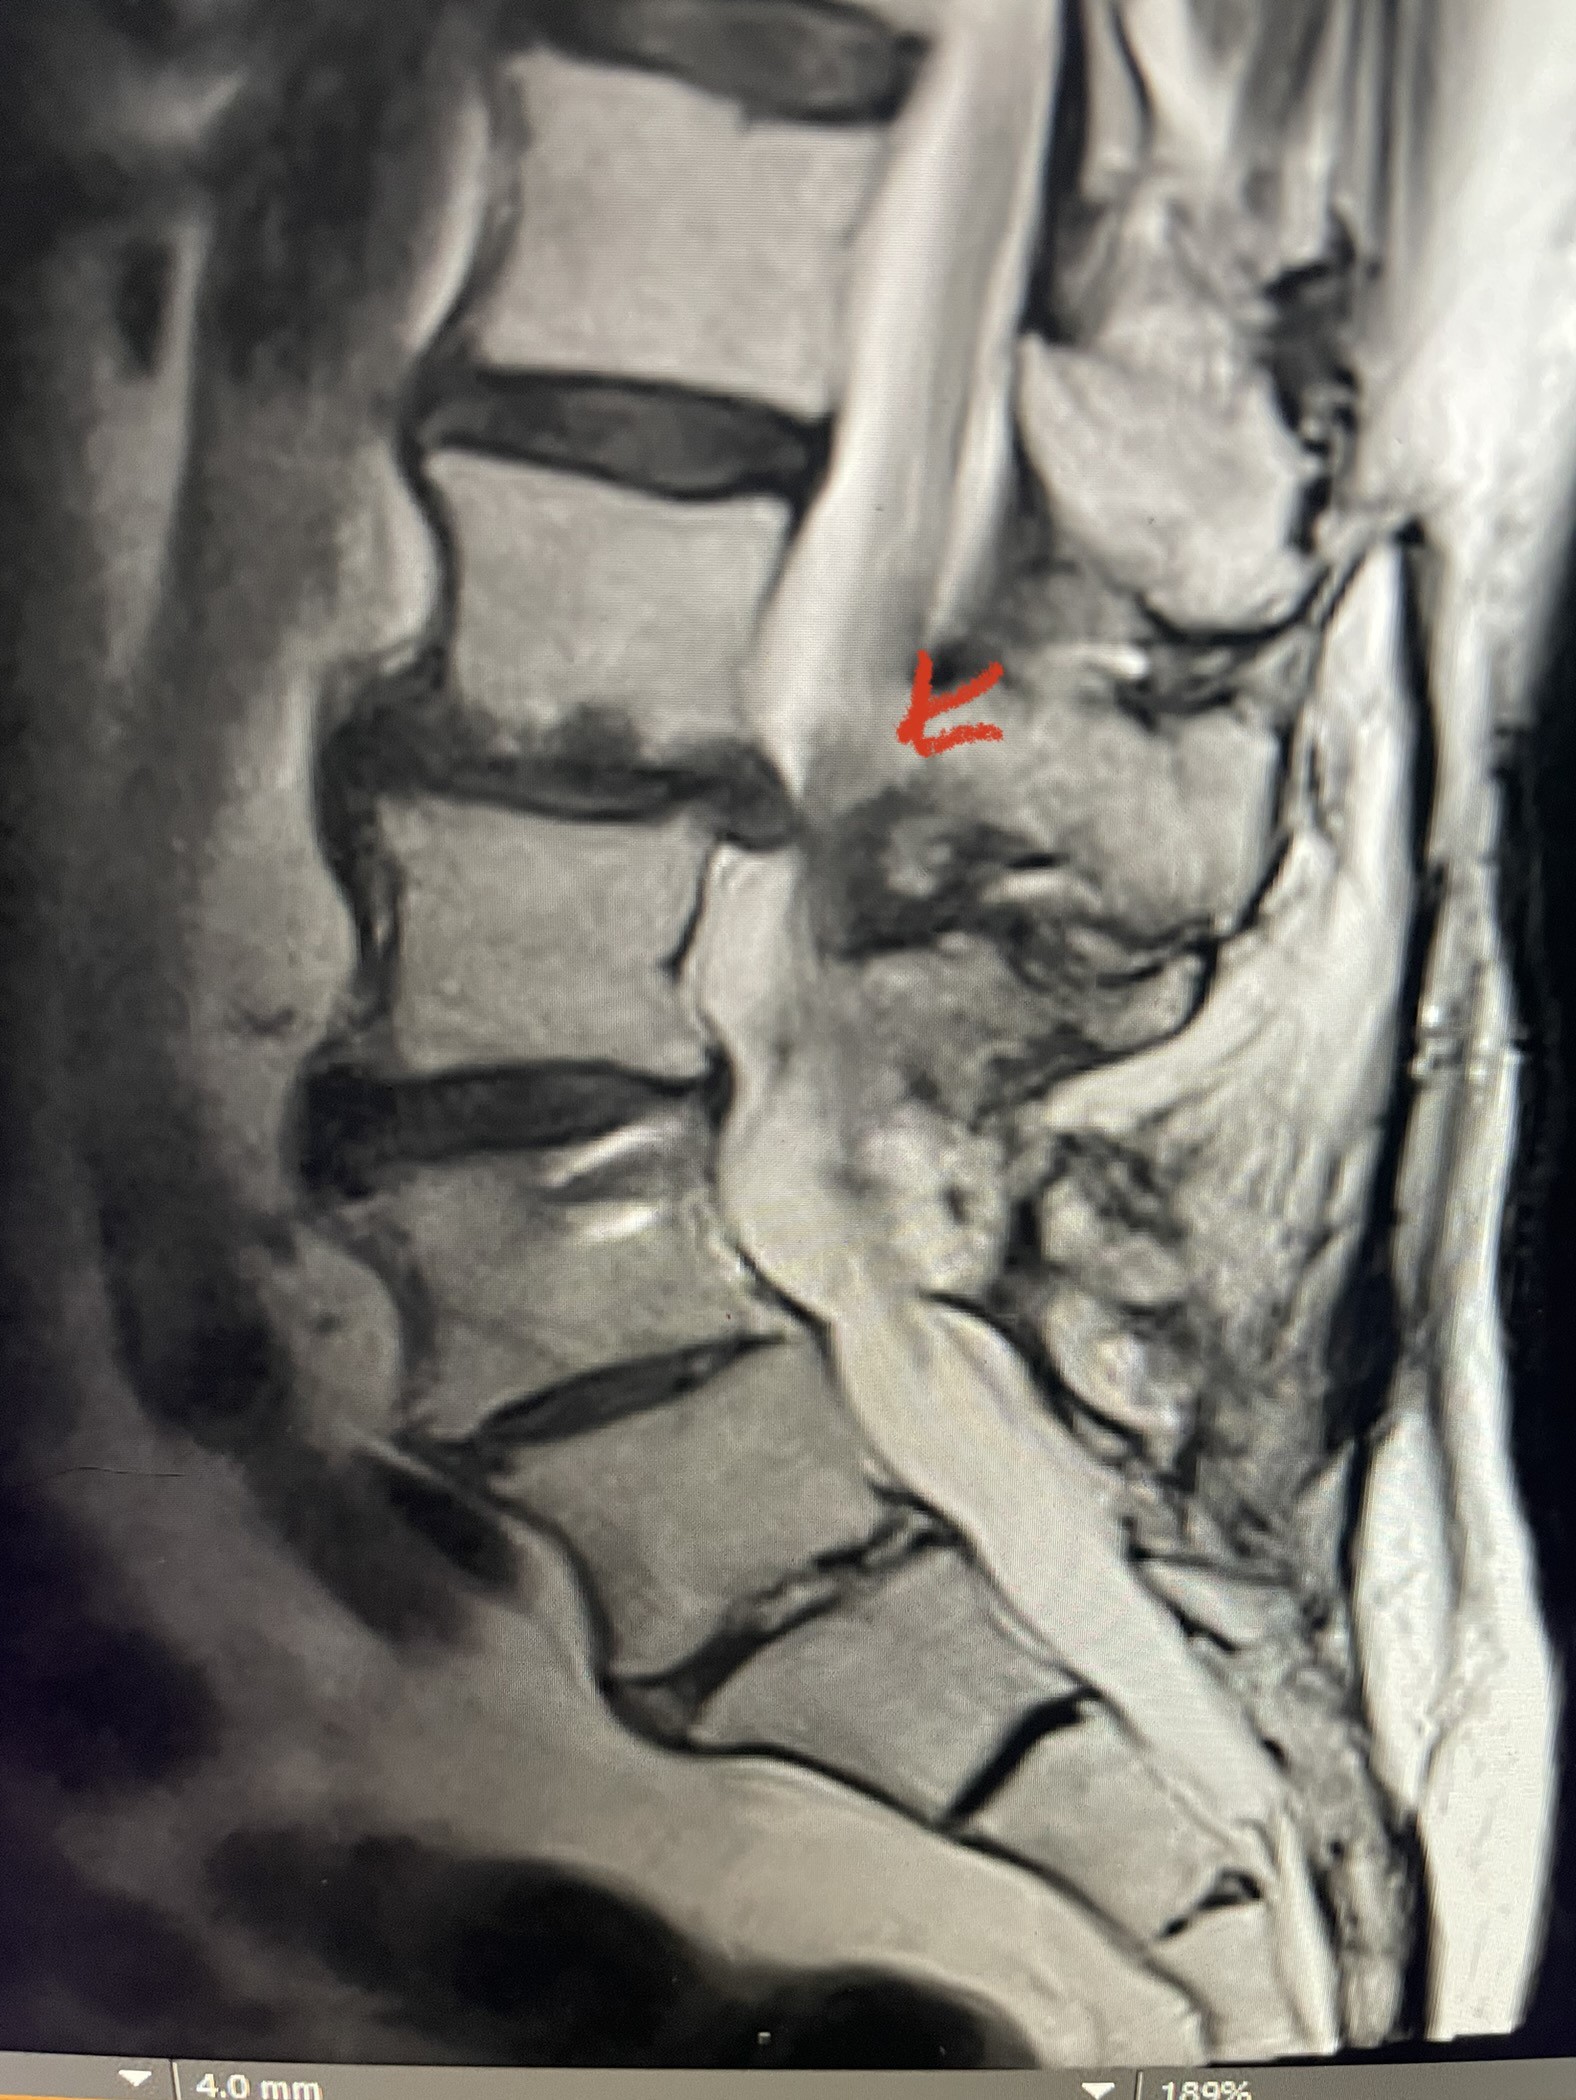

This 54-year-old morbidly obese female presents with progressive back and leg pain and quadriceps weakness. She had no diabetes. She failed all means of conservative management including physical therapy and epidural injections. On imaging she had severe stenosis at L3-4 with a disc protrusion and a slight grade 1 spondylolisthesis at L3-4 (Fig 1). We performed dynamic lumbar x-rays which demonstrated instability at L3-4 and L4-5 (Fig 2). The patient wished to have surgery. We performed an L2-4 decompressive laminectomy and L3-5 in situ fusion because of her instability. Post operatively the patient had relief of leg pain, although the patient was slow to mobilize.

Figs. 1a: Sagittal lumbar T2-weighted MRI demonstrating severe lumbar stenosis with a slight grade 1 at L3-4 and a disc protrusion (red arrow )